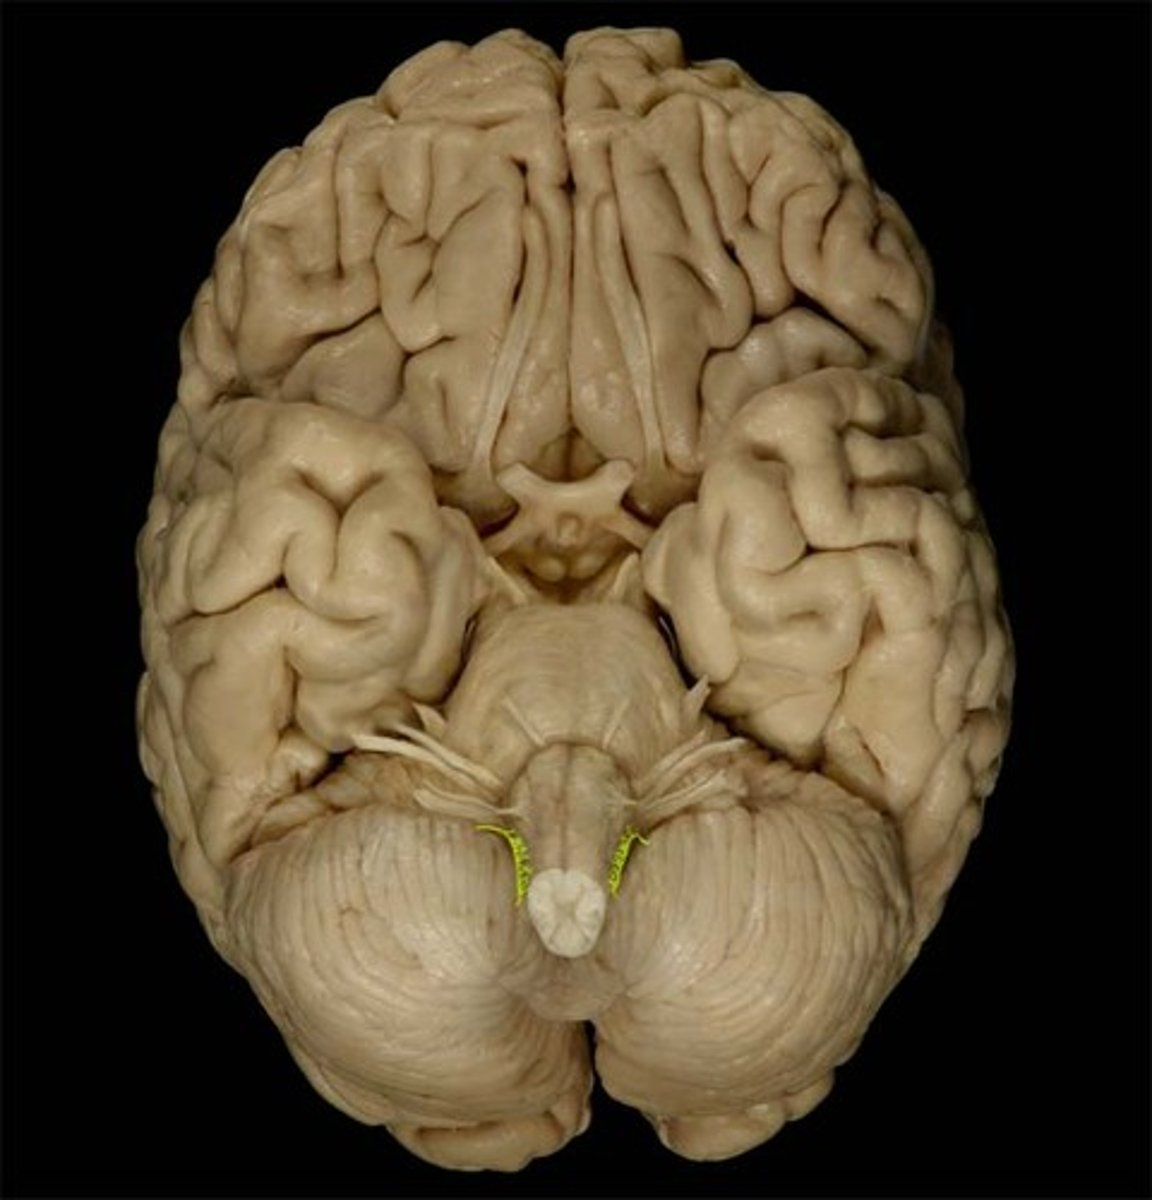

trochlear nerve (CN IV)

Motor cranial nerve that controls movement of the eye inferiorly and laterally; innervates superior oblique muscle